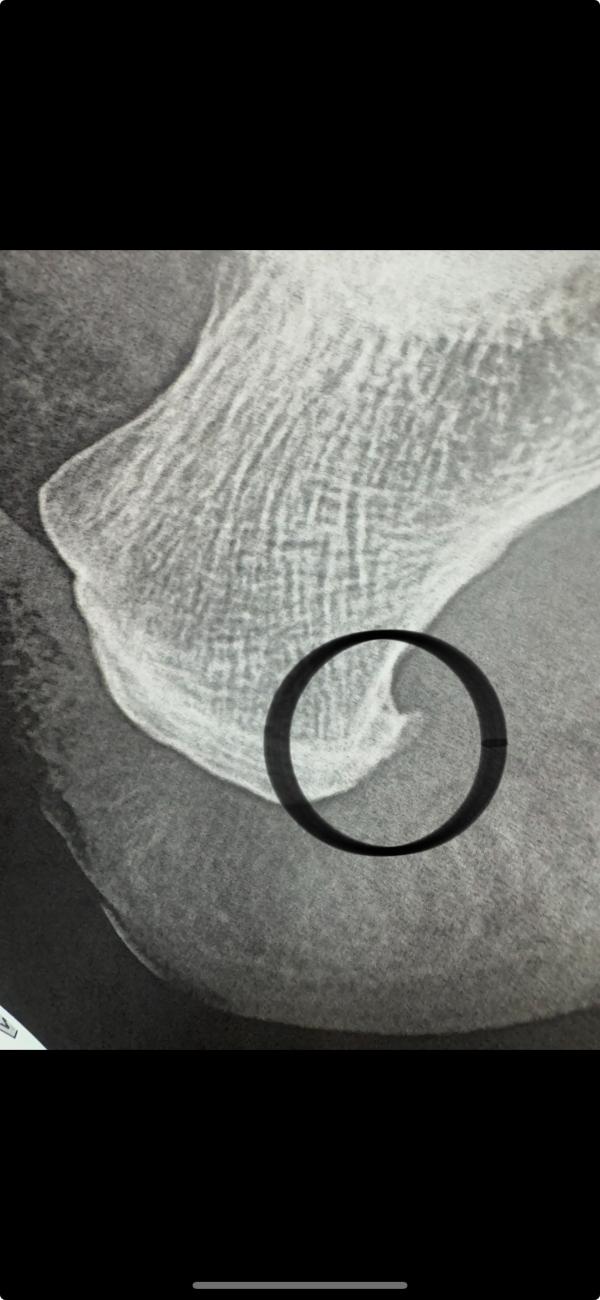

Вопросы 35+. Беда пришла, откуда не ждали🥴. Девочки, кто сталкивался с пяточной шпорой? Два месяца мучалась, думала, что просто неудобная обувь или растяжение, в итоге сделали ренгтген - а там это хрень. Что помогло? К какому доктору идти?